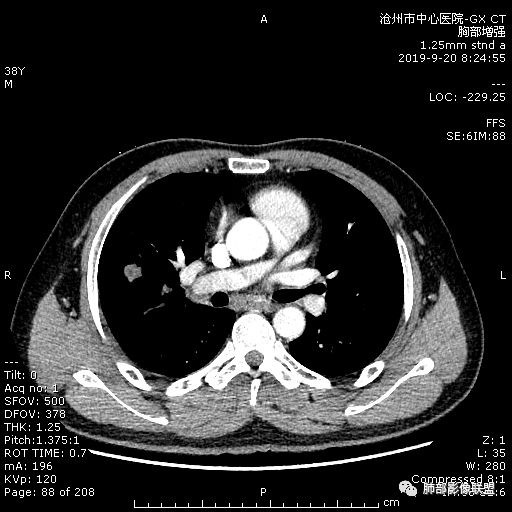

年轻男性,咳嗽2月,痰中带血,胸痛,炎症指标稍高,肿标正常。影像,右肺上叶不规则团块影,浅分叶,伴边界不清磨玻璃影,从外周向内分布,局部胸膜增厚,病灶中央坏死,坏死边界尚清,空洞形成,空洞内壁光滑;考虑炎性肉芽肿性病变,结核可能,鉴别恶性肿瘤及真菌感染。病灶分布特点不考虑隐球。

右肺上叶不规则病灶,密度不均,有分叶,边缘不清,中央有坏死,坏死壁尚光滑,增强壁有强化,病灶有外朝内,整体收缩为主,慢性病程,考虑炎性病变,肺脓肿或者结核,淋巴结肿大,支气管截断,胸膜脂肪间隙变窄,加个鉴别恶性肿瘤。

38岁,男性,慢性咳嗽2月,右胸痛8天,无发热;白细胞高,肿瘤标志物不高;右上肺不规则块状影,周围有磨玻璃影,边界清,整体有膨胀感,分叶,与胸膜糊墙,并见栽赃,增强肿块中央坏死,周边强化。综合考虑,考虑恶性,鳞癌可能。

38岁,男性,慢性咳嗽2月,右胸痛8天,无发热。白细胞高,肿瘤标志物不高。右上肺不规则块状影,周围有磨玻璃影,边界模糊,整体有膨胀感,分叶,与胸膜糊墙,可疑栽赃,增强肿块中央坏死,边界清,周边强化明显,强化区有低密度影,壁不规则,跨叶生长,支气管截断,伴支气管扩张,综合考虑腺癌

中年男性,咳嗽2月,伴胸痛8天,少许痰血,无发热中性粒明显增高,低氧,肿标不高,右肺上叶不规则实性肿块,深分叶,局部凹陷呈月牙铲改变,多坏死,多空泡,前段支气管分支似见堵塞,2R、4R、10R和7区淋巴结肿大。考虑肺癌可能,建议支气管镜活检

良孑: 晨读病例,右上肺不规则实变,边界模糊,内可见多发坏死灶,腔内坏死壁厚薄不均,有支气管截断,强化时病灶内血管受累,右肺门淋巴结肿大,从影像上看恶性鳞癌征象较多,但病变明显强化,且坏死壁是均匀强化,炎性标志物高,患者年龄较轻,病史较长,病灶内多个坏死液化灶且内缘光整,综和判断,首先考虑亚急性肺脓肿,其次考虑鳞癌

3.ct表现:肺脓肿可呈结节状或团块状,有时呈不规则形,气道来源肺脓肿常单发,血行来源常多发,边缘模糊,部分病灶周围可见片状肺实变及磨玻璃影;病灶中央为液化坏死区,若脓肿与支气管相通,脓液排出可形成空洞,空洞内可形成液平;急性肺脓肿内壁多不规则;慢性肺脓肿洞壁较厚,一般不规则或形成多房空洞:CT增强扫描空洞壁可见强化,空洞壁为纤维肉芽组织,呈典型的环形强化;慢性肺脓肿周围可有较广泛的纤维索条影,可伴支气管扩张.肺

气肿或胸膜增厚表现。

今天病例坏死周围也可以看到明显强化的脓肿壁,只是局部脓肿壁不规则模糊,部分脓肿壁规则清楚。